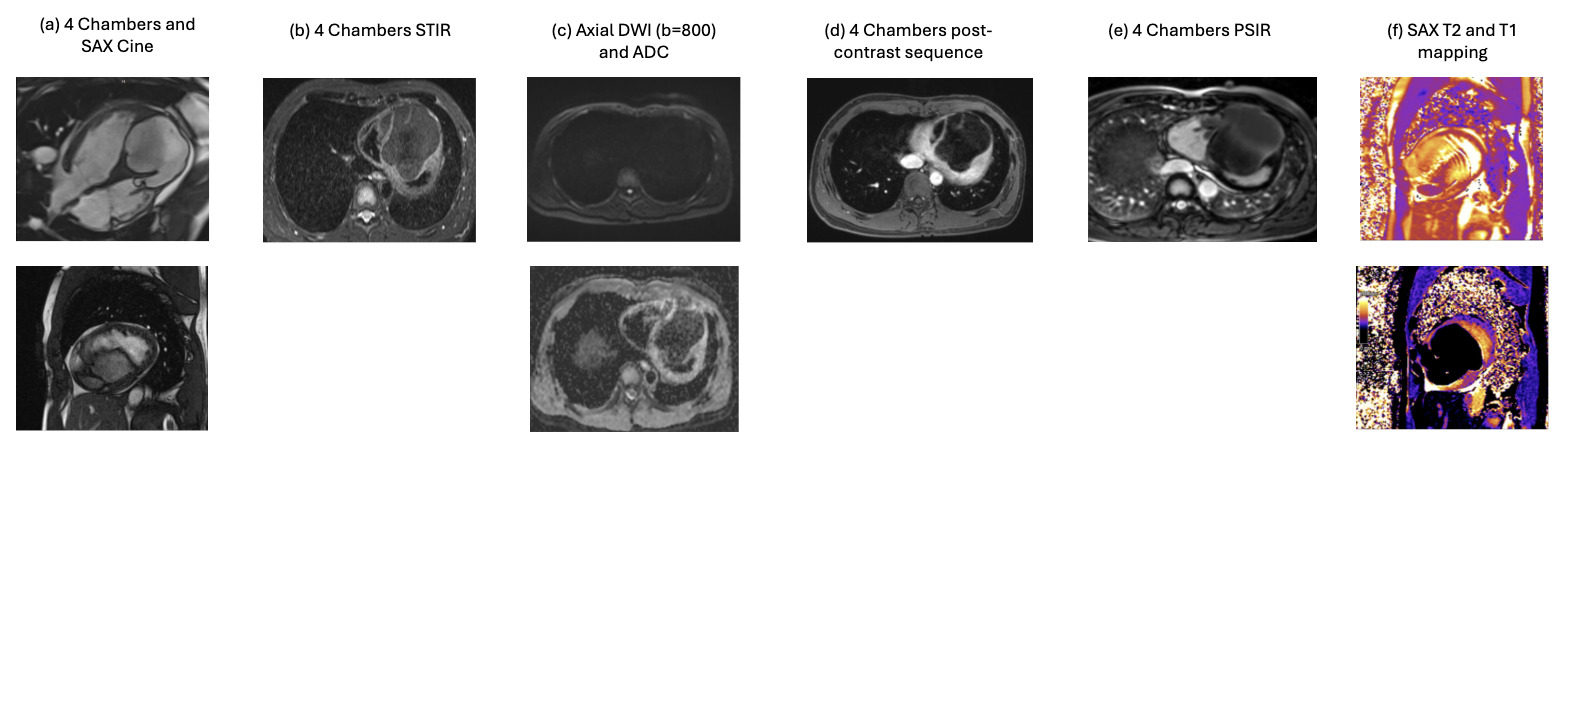

Figure 2. Multimodality CMR and tissue characteristics. (a) Four-chamber and short-axis cine sequences demonstrate a large multilobulated (septated) mass occupying the apical left ventricle and protruding into the right ventricular cavity. (b) Four-chamber STIR imaging shows homogeneous suppressed signal without edema. (c) Axial diffusion-weighted imaging (b = 800) and ADC map confirm absence of diffusion restriction. (d) Four-chamber post-contrast sequence shows no abnormal enhancement. (e) Four-chamber PSIR late gadolinium enhancement sequence confirms absence of contrast uptake, consistent with a benign lesion. (f) Short-axis T1 and T2 mapping demonstrate relaxation times compatible with fat-containing tissue (comparable with subcutaneous fat). Abbreviations: ADC = Apparent Diffusion Coefficient; CMR = Cardiac Magnetic Resonance; DWI = Diffusion-Weighted Imaging; PSIR = Phase-Sensitive Inversion Recovery; SAX = Short Axis; STIR = Short Tau Inversion Recovery..jpg)